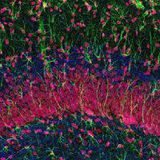

Nutmeg liver is chronic passive venous congestion. It is due to RHF, IVC obstruction or portal hypertension. Macroscopically liver is enlarged and cut surface give nutmeg appearance. Microscopically see the central ischaemic coagulative necrosis and peripheral fatty change in hepatocyte.